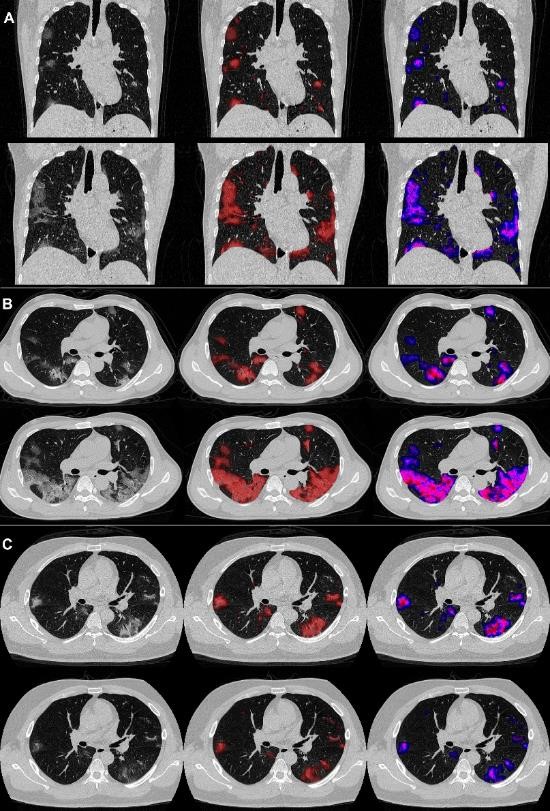

研究中,联合科研课题组针对上海市公共卫生临床中心确诊的134位COVID-19患者,使用全卷积神经网络AI算法自动计算肺炎病变的三个定量CT特征,包括磨玻璃病变体积占比(PGV),实性病变体积占比(PCV),以及磨玻璃-实性过渡密度区病变体积占比(PSV)。